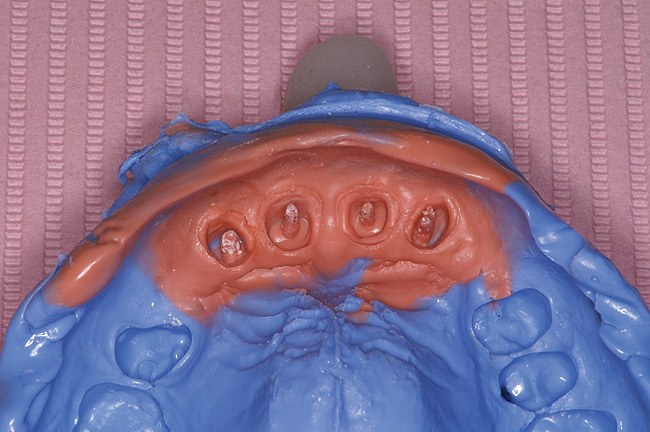

Although there have been trends to use prefabricated post systems, there are specific clinical situations where a morphological, custom-cast post-and-core with a high-noble alloy would be beneficial. A cast post-and-core is the restoration of choice for clinical circumstances where there is limited tooth structure available to develop a ferrule when preparing the tooth for a crown or when there is insufficient tooth structure available to create an anti-rotational design to the core on a prefabricated post.6 Mandibular incisors, maxillary incisors, and canines that have minimal amounts of coronal tooth structure remaining are good candidates for a custom, morphological cast-gold post and core.4-6,69 There are two techniques that can be used when fabricating a custom-made, laboratory-fabricated post. A custom-made post can be fabricated directly in the mouth on the tooth preparation using a plastic post that is burnt-out during the metal-casting or ceramic-pressing process. A more predictable technique uses an impression of the tooth preparation and the root canal (Figure 9A and Figure 9B). This saves chairtime. The impression is poured by the laboratory and casting patterns are made on the master cast by the laboratory technician for casting in either metal or ceramic (Figure 10). The final custom-made post is then cemented into the root canal (Figure 11).

Figure 9a  Maxillary incisors (with short roots) after endodontic treatment, crown margin, and post preparation.

Figure 9a

Figure 9b  Impression of the crown and root canal post preparation.

Figure 9b

Figure 10  Cast gold post and cores for teeth No. 7 through 10 on the master cast.

Figure 10